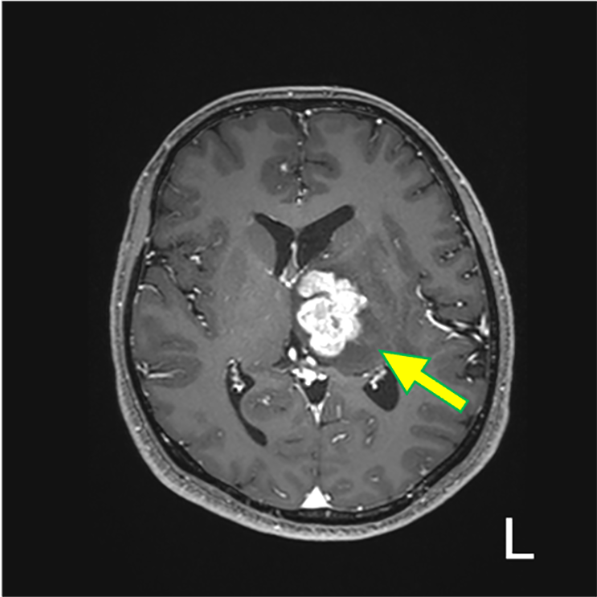

図5.造影後 T1WI (Tra.)

T2強調像で認めた分葉状の実質部が強く造影されている。内部に小さな造影欠損を伴う(矢印)。松果体原発では無いと考えられる。

図6.造影後 T1WI (Cor.)

水平断同様に内部に小さな造影欠損を伴い、強く造影される病変を認める(矢印)。